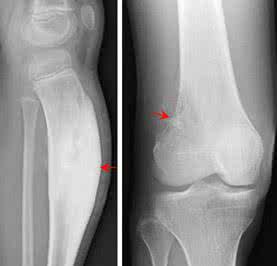

关节损伤包括软组织损伤和骨损伤。关节的骨刺经常与关节内骨折有直接关系。由于骨折复位不完全,造成关节软骨面不平整,从而产生创伤性关节炎。对于关节内骨折的患者,如果能够及时治疗,作到解剖复位,完全可以避免创伤性关节炎和关节骨质增生的发生。